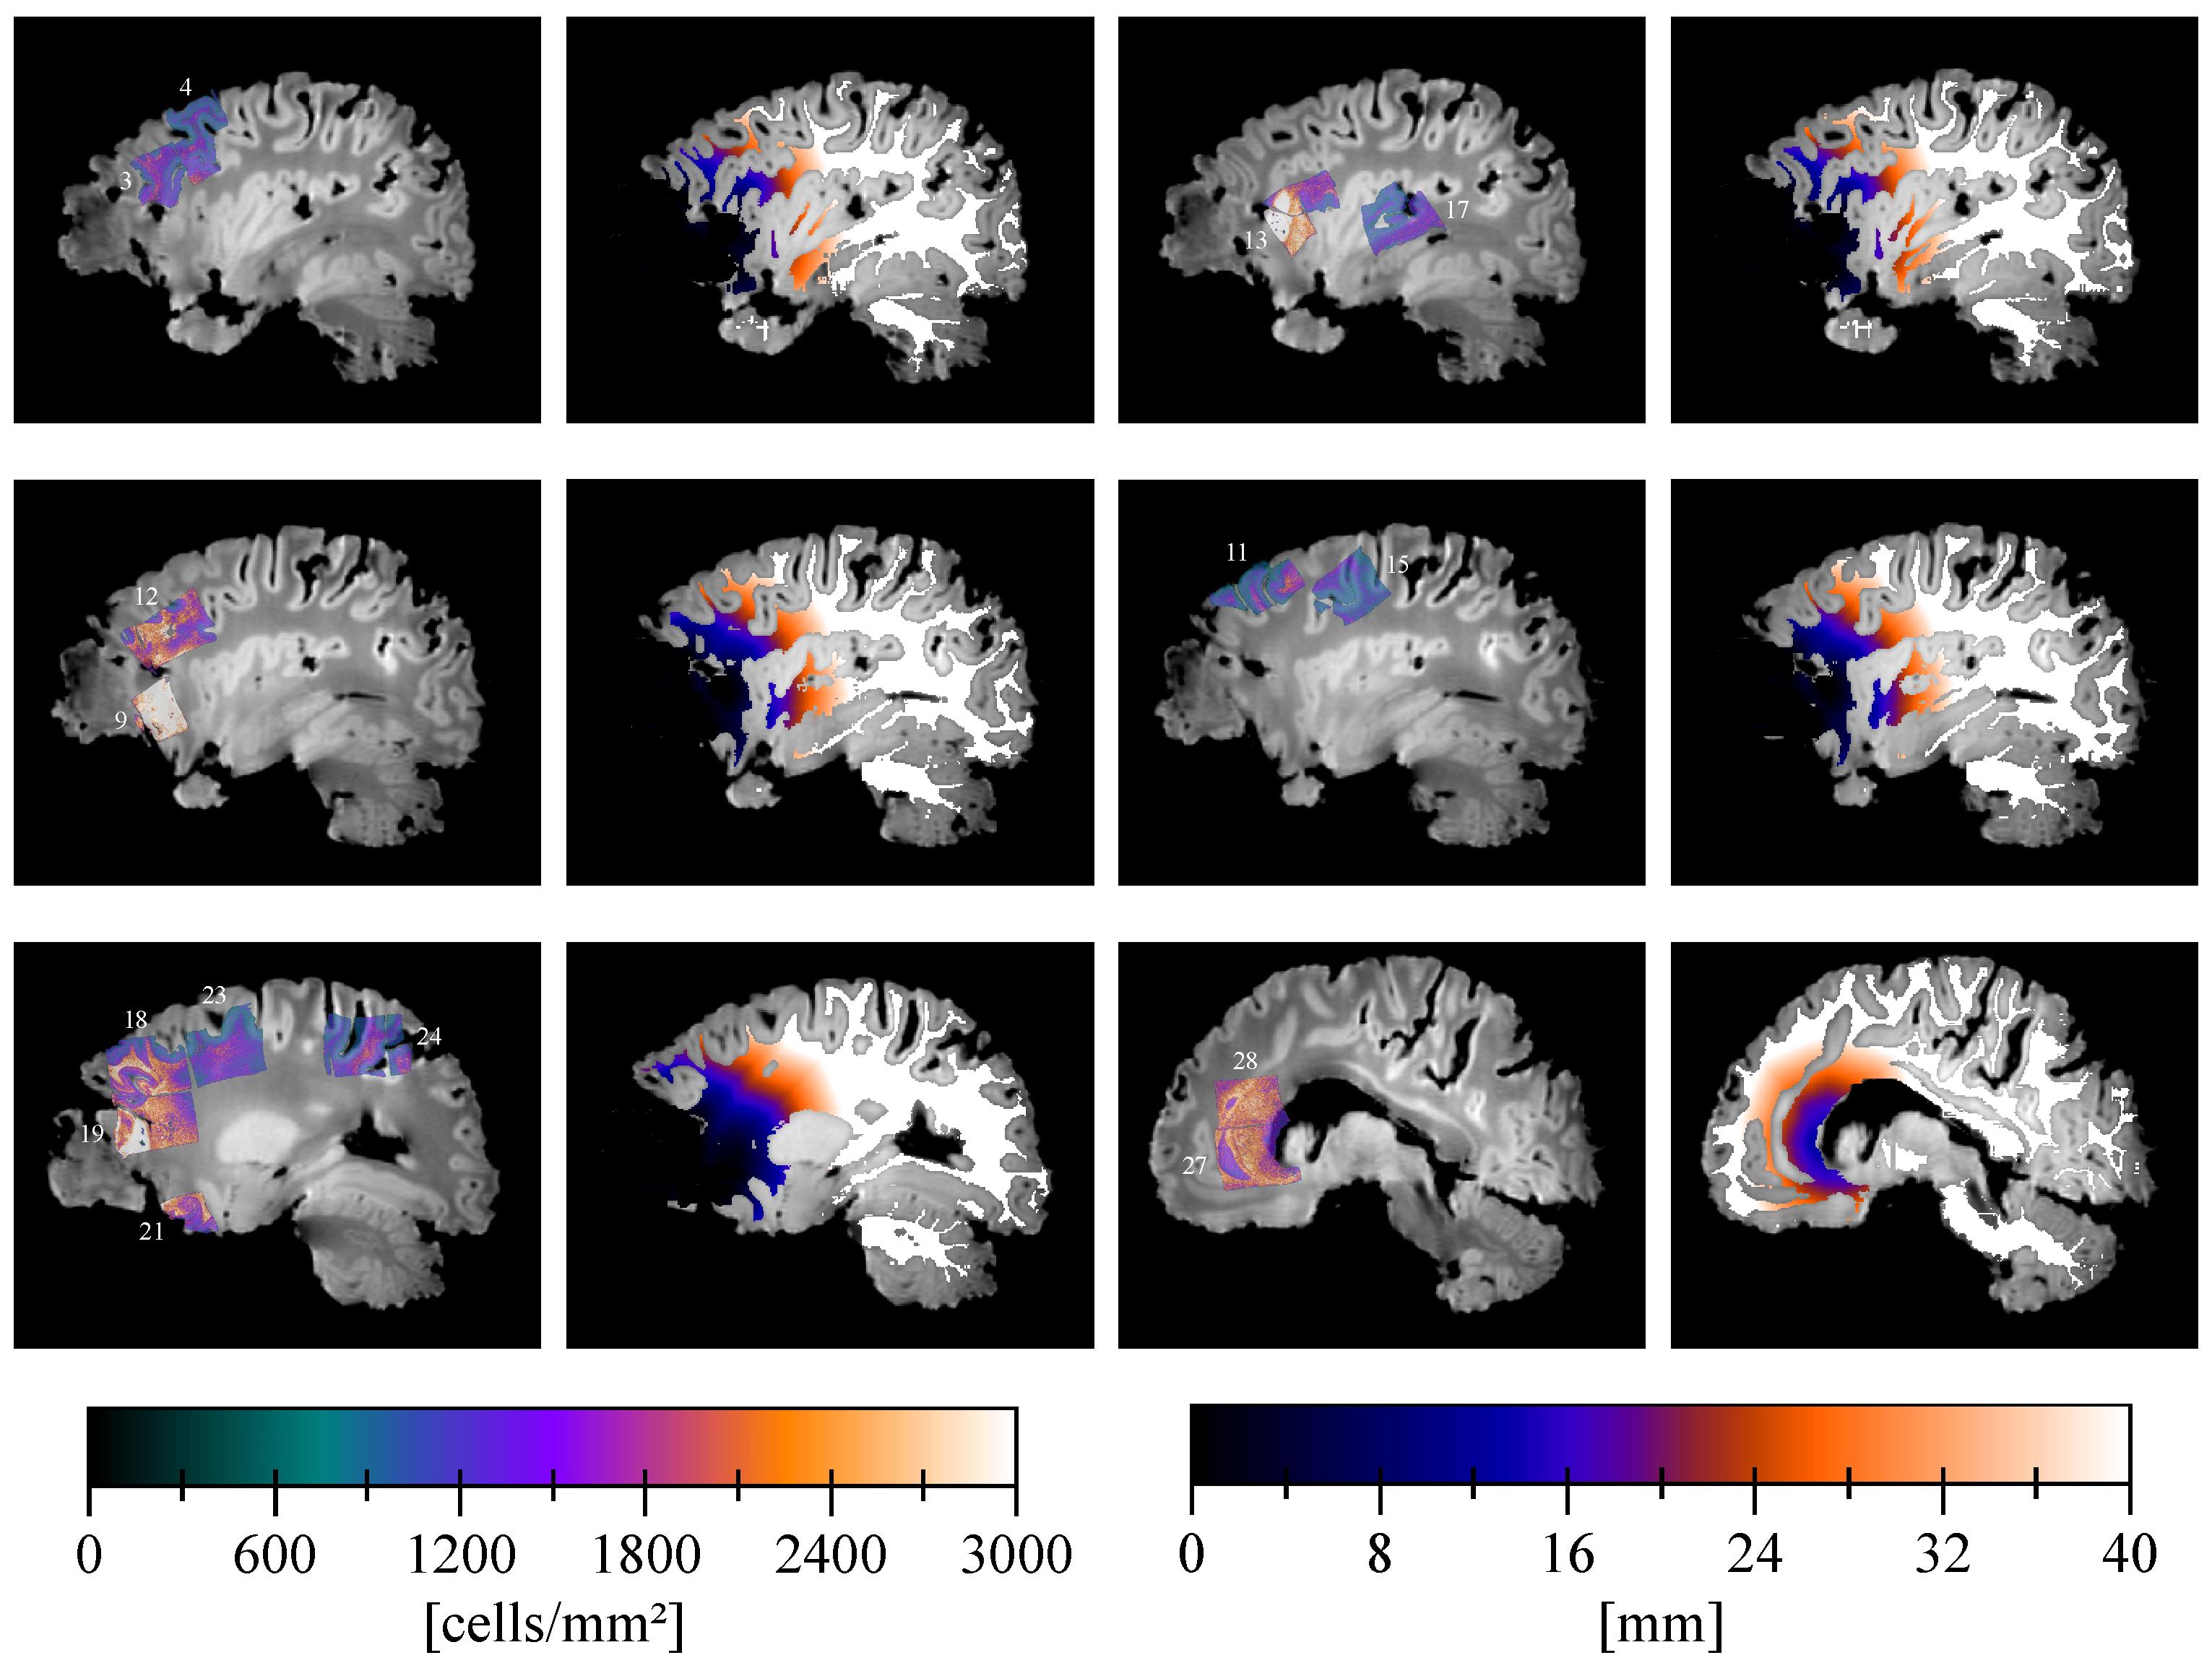

3. Results

| Cell Density [ ] | Distance [] | |||||||||

|---|---|---|---|---|---|---|---|---|---|---|

| Block | PPN | Tumor Cells | GVP | Edema | Min | Max | Mean | Min | Max | Mean |

| 1 | No | No | No | No | 1.08 | 20.46 | 11.77 | 33.40 | 40.40 | 34.95 |

| 2 | No | No | No | No | 2.25 | 23.88 | 13.80 | 35.05 | 46.76 | 40.12 |

| 3 | No | Infiltrative (susp.) | No | Yes | 1.52 | 25.25 | 14.96 | 7.24 | 21.18 | 14.00 |

| 4 | No | No | No | No | 1.36 | 20.64 | 12.50 | 29.36 | 41.66 | 36.84 |

| 5 | No | No | No | Yes | 1.19 | 24.85 | 15.40 | 11.74 | 30.27 | 21.57 |

| 6 | No | Infiltrative (susp.) | No | No | 3.72 | 28.44 | 18.70 | 32.92 | 40.35 | 36.52 |

| 7 | No | Infiltrative (susp.) | No | Yes | 0.89 | 38.95 | 21.44 | 38.59 | 61.70 | 49.04 |

| 8 | Yes | Block | Yes | No | 3.37 | 37.29 | 23.65 | 0.50 | 5.17 | 2.71 |

| 9 | Yes | Infiltrative | Yes | Yes | 1.02 | 44.37 | 31.71 | 0.50 | 4.72 | 1.91 |

| 10 | No | Infiltrative (susp.) | No | Yes | 5.52 | 37.15 | 25.53 | 0.50 | 3.71 | 1.06 |

| 11 | No | No | No | No | 1.73 | 25.68 | 15.21 | 19.85 | 38.74 | 30.74 |

| 12 | No | Infiltrative | Yes | Yes | 0.89 | 36.08 | 19.70 | 0.50 | 31.46 | 14.24 |

| 13 | Yes | Block | Yes | No | 1.40 | 52.46 | 21.69 | 0.50 | 22.85 | 9.72 |

| 14 | No | No | No | No | 1.10 | 19.25 | 11.78 | 17.73 | 32.20 | 25.51 |

| 15 | No | No | No | Yes | 2.08 | 22.90 | 11.41 | 28.63 | 54.74 | 40.14 |

| 16 | No | No | No | No | 0.99 | 26.47 | 13.52 | 20.37 | 48.79 | 35.91 |

| 17 | No | No | No | No | 1.42 | 23.69 | 13.10 | 28.30 | 56.12 | 42.88 |

| 18 | No | No | Yes | Yes | 2.46 | 39.29 | 20.71 | 7.94 | 27.01 | 16.83 |

| 19 | Yes | Block | Yes | Yes | 0.99 | 44.12 | 19.82 | 0.50 | 18.50 | 6.92 |

| 20 | Yes | Block | Yes | No | 6.25 | 61.05 | 28.40 | 0.50 | 7.37 | 2.06 |

| 21 | No | Infiltrative | Yes | Yes | 4.75 | 34.20 | 23.05 | 0.50 | 14.62 | 7.70 |

| 22 | No | No | No | Yes | 0.86 | 30.37 | 10.79 | 2.99 | 36.87 | 21.39 |

| 23 | No | No | No | No | 0.94 | 25.61 | 13.23 | 21.14 | 49.61 | 34.48 |

| 24 | No | No | No | No | 1.37 | 26.72 | 13.72 | 57.27 | 90.93 | 71.08 |

| 25 | No | Infiltrative (susp.) | No | Yes | 0.87 | 39.07 | 21.03 | 1.71 | 21.41 | 10.87 |

| 26 | Yes | Block | Yes | Yes | 6.21 | 54.24 | 22.79 | 0.50 | 8.81 | 2.96 |

| 27 | No | No | No | Yes | 0.93 | 37.96 | 21.33 | 12.74 | 30.35 | 18.40 |

| 28 | No | No | No | No | 0.95 | 34.79 | 20.76 | 14.35 | 35.85 | 22.57 |